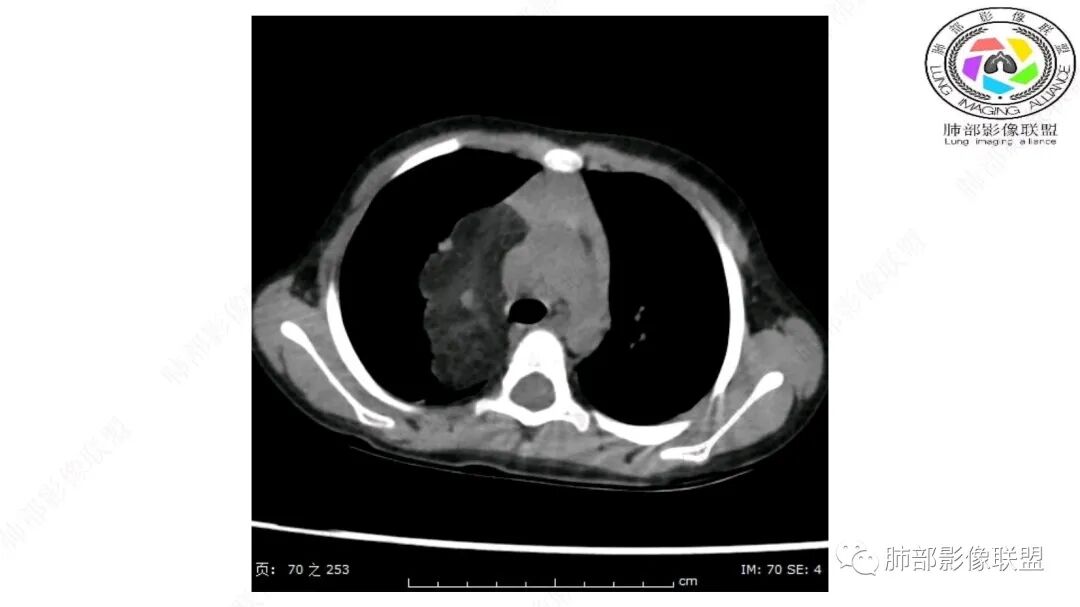

病灶属于交界区,主体位于肺内,占位效应明显,前方突入胸壁,胸腺受压变形,胸膜显示欠清楚;病灶包绕上叶肺动脉;似乎有体动脉供血。符合肺内的点:包绕上叶肺动脉分支;符合纵隔的点:前方似乎突入胸壁,与胸腺关系比较密切,但是与上腔静脉的关系提示病灶不支持纵隔来源,前纵隔的常规会将上腔静脉受压后移、外移,这是不符合的。

内部血管明显,部分病灶密度增高,单纯脂肪瘤不支持。可惜的是:没有提供CT值:是否强化?如果强化,警惕恶性;胸腺肯定不符合,胸腺会将上腔静脉朝后推移。

1.右上肺-纵隔交界区巨块影,主体位于右肺一侧,紧贴胸腺、头臂干、右锁骨下动脉、上腔静脉、奇静脉等,不能分离,但病灶整体边界清楚。注意上述相邻腔静脉等结构未见受压变形,纵隔亦未见明显向左推移,至少提示两点:

1)病灶相当柔软。

2)位于纵隔内或纵隔胸膜的可能性较小,因为受纵隔胸膜反作用力影响不明显。

2.肺动脉穿行也许是肺内来源最重要支持点!

CT扫描对脂肪类肿瘤常有独到价值。肿块孤立、边界清楚,未见周围浸润,较均匀脂肪样低密度,高度提示为良性!